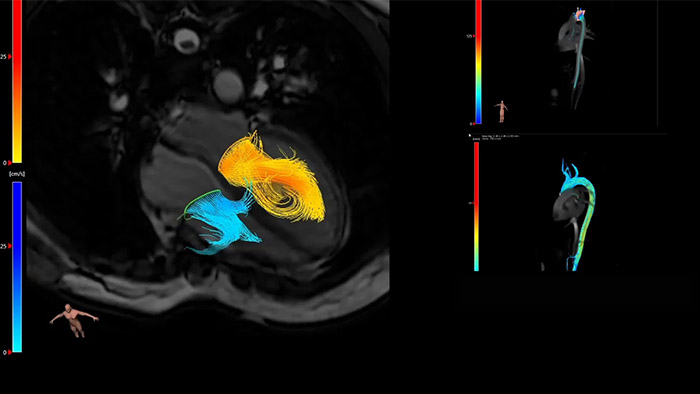

IntelliSpace Portal MR Caas7,8 A solução de pós-processamento 4D Flow permite a geração de reconstruções de volume 3D, para visualizar e avaliar o fluxo sanguíneo em estruturas cardiovasculares, incluindo válvulas cardíacas, câmaras e vasos, com base nas imagens de RM 4D Flow cardiovascular.